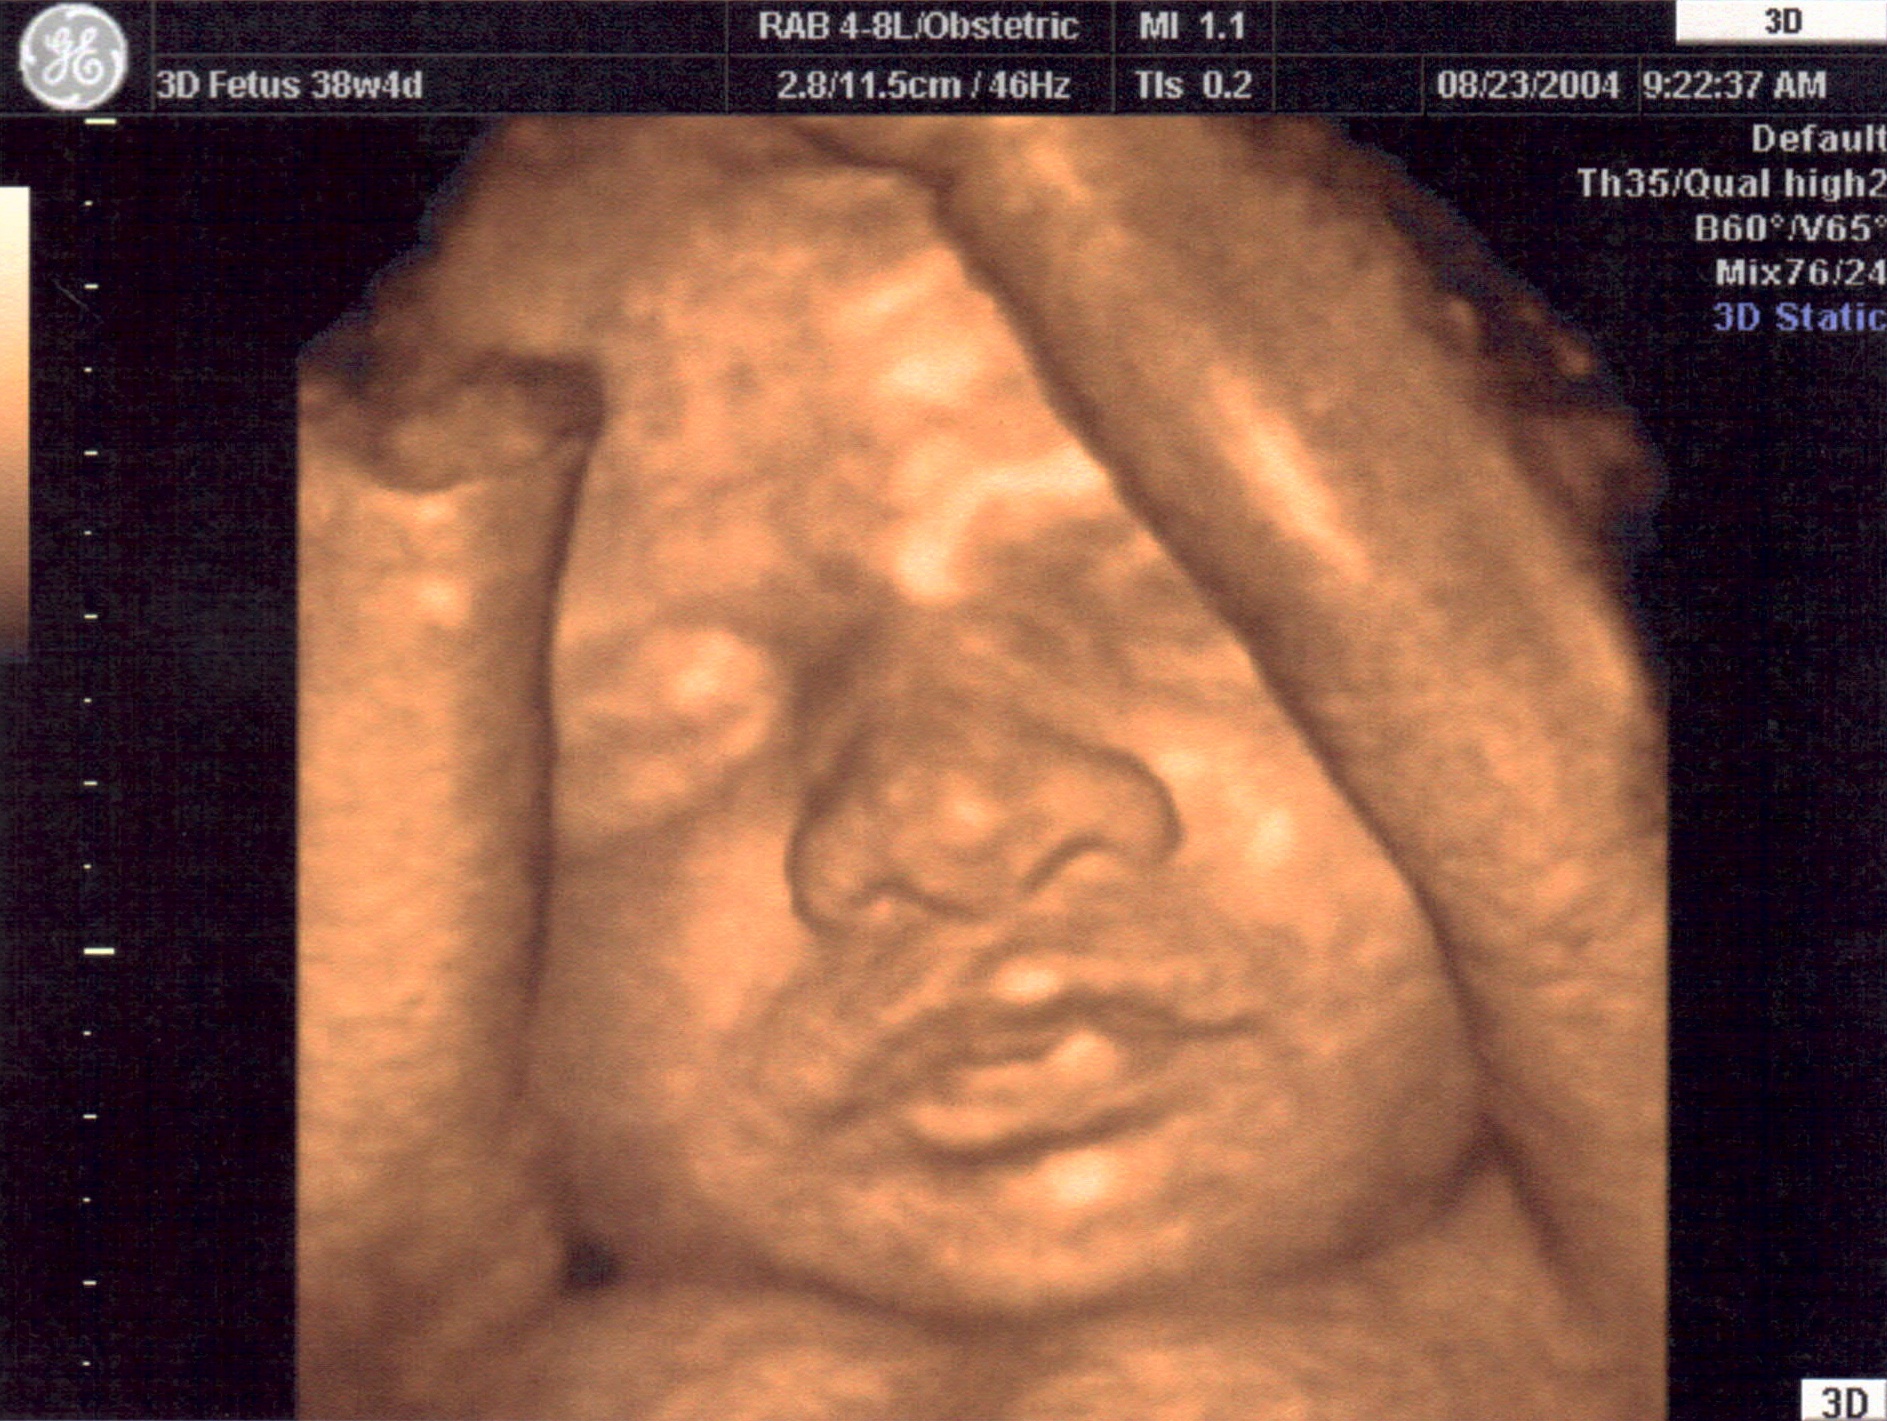

Gallery ECO